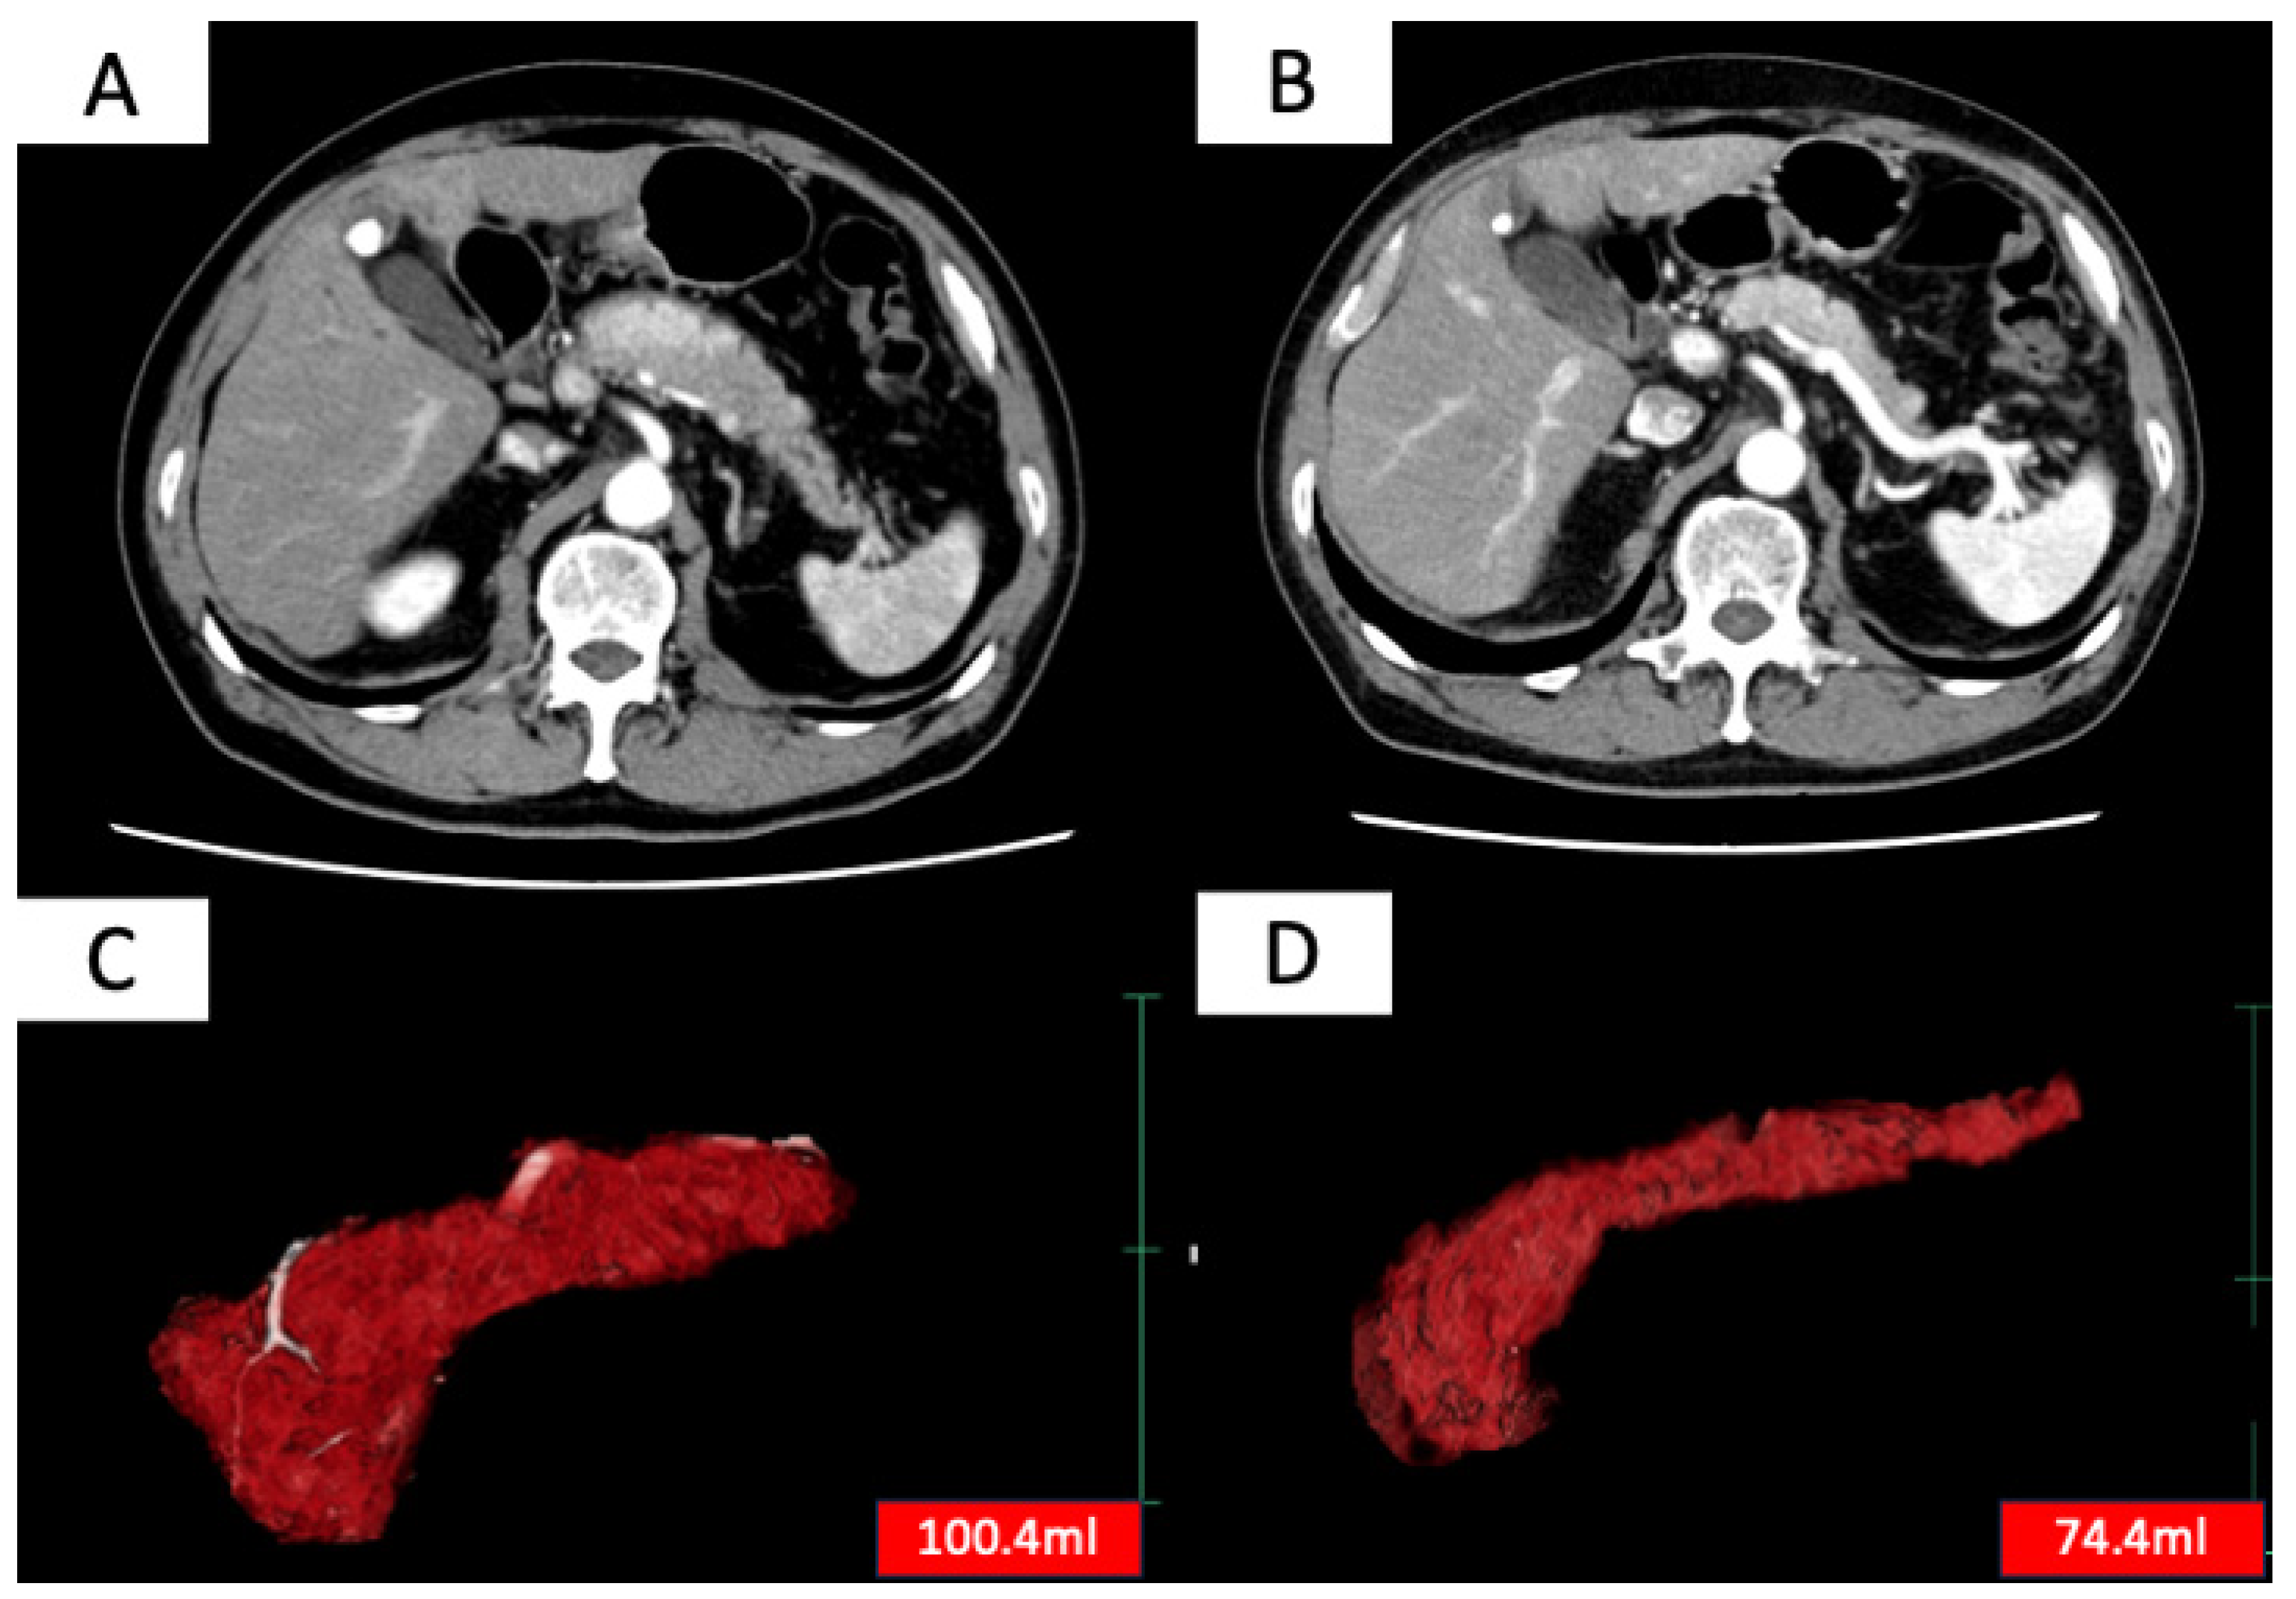

| Pancreas volume before start of treatment, mL (range) | 76.1 (26.1–194) | 76.8 (26.1–129.3) | 72.5 (32.3–194) | 0.71 |

| Pancreas volume 0.5–1 year after start of treatment, mL (range) | 33.9 (9–118) | 29.0 (9.0–84.8) | 37.3 (14.2–118) | 0.13 |

| Reduction rate of pancreas volume, % | 54.5 (0.4–85.9) | 58.0 (0.4–86.9) | 49.5 (10.6–80.5) | 0.31 |

| Pancreas volume before treatment, mL (range) | 67.1 (26.1–194) | 79.2 (31.8–129.3) | 0.06 |

| Pancreas volume 1 year after treatment, mL (range) | 23.3 (9.0–54.7) | 38.0 (14.8–118) | 0.002 |

| Reduction rate of pancreas volume, % (range) | 60.2 (24.5–86.9) | 48.4 (0.4–80.5) | 0.04 |